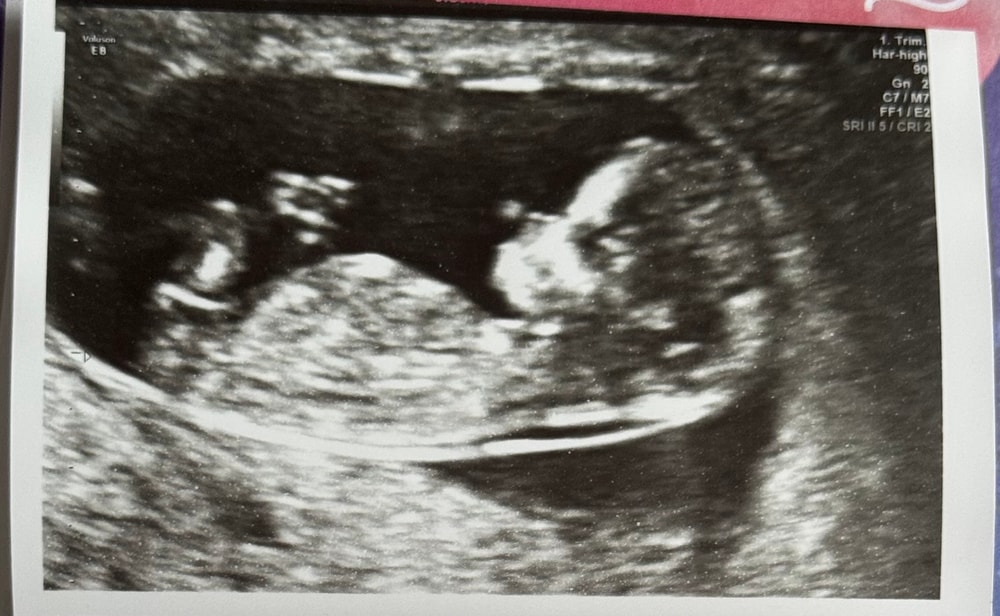

Первый скрининг 12 недель

Наши будни, наши неделькиЭтот день был очень волнительным, но прошел замечательно) По узи все хорошо, в риск заболеваний не попадаем, кровь нипт тоже сдали. По узи поставили 12+1н на сроке 11+6н пдр на 19.12.2025 🤗 пол не сказали, но я насмотрелась видео, как определять и мне кажется, что это барышня)